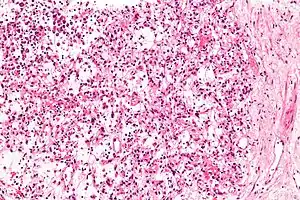

| Micrograph of an inflammatory myofibroblastic tumour of the kidney. Kidney biopsy. H&E stain. | |

Histopathologic examination of the tumors in IMT generally reveals myofibroblastic spindle cell sheets in a myxoid background (i.e. a background matrix containing gelatinous mucopolysaccharides and non-sulfated glycosaminoglycans); the matrix also contains inflammatory cells, particularly plasma cells and lymphocytes occasionally mixed with eosinophils and neutrophils. The epithelioid inflammatory myofibroblastic sarcoma subtype of IMT shows sheets of epithelioid to round cells within a myxoid (i.e. appears blue or purple compared to the normal red appearance of connective tissue when appropriately H&E stained and examined under the microscope), collagenous, or mixed myxoid-collagenous matrix, <5% spindle cells, and an inflammatory cell infiltrate that in most cases consists predominantly of neutrophils or, less often, small lymphocytes or eosinophils; plasma cells occur in only a minority of EIMS cases. The neoplastic cells in the tumors of 50% to 60% of IMT cases[2] and 100% of EIMS cases[3] express an ALK fusion protein. Other genetic abnormalities occur in these cells. Testing for the presence of the ALK fusion protein and other genetic abnormalities (see next section) can help diagnose IMT.[31]